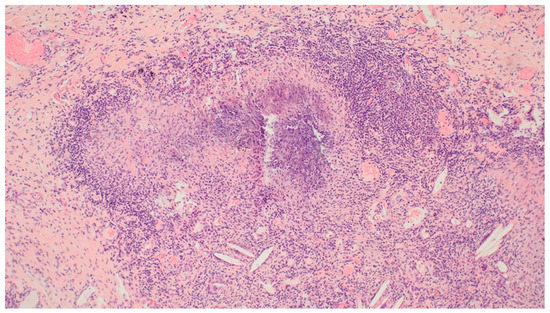

3. Results